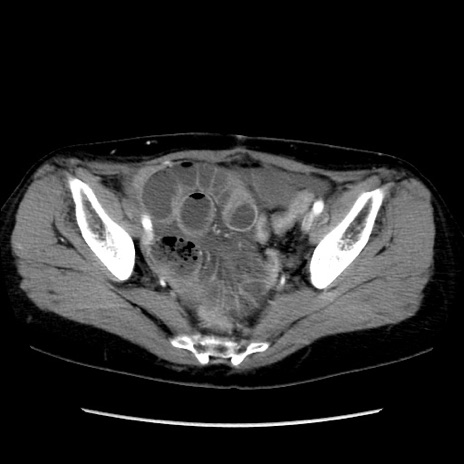

矢状断像

【症例】40歳代 女性

【主訴】上腹部痛、嘔気・嘔吐

【現病歴】約9時間前頃から急に上腹部痛、嘔気、嘔吐が出現。改善しないため救急要請。

【既往歴】子宮頚癌(広汎子宮全摘術、放射線療法)、腸閉塞

【身体所見】腹部:平坦、軟、腸雑音亢進、上腹部を中心に腹部全体に圧痛あり。

【データ】WBC 8400、CRP 0.03